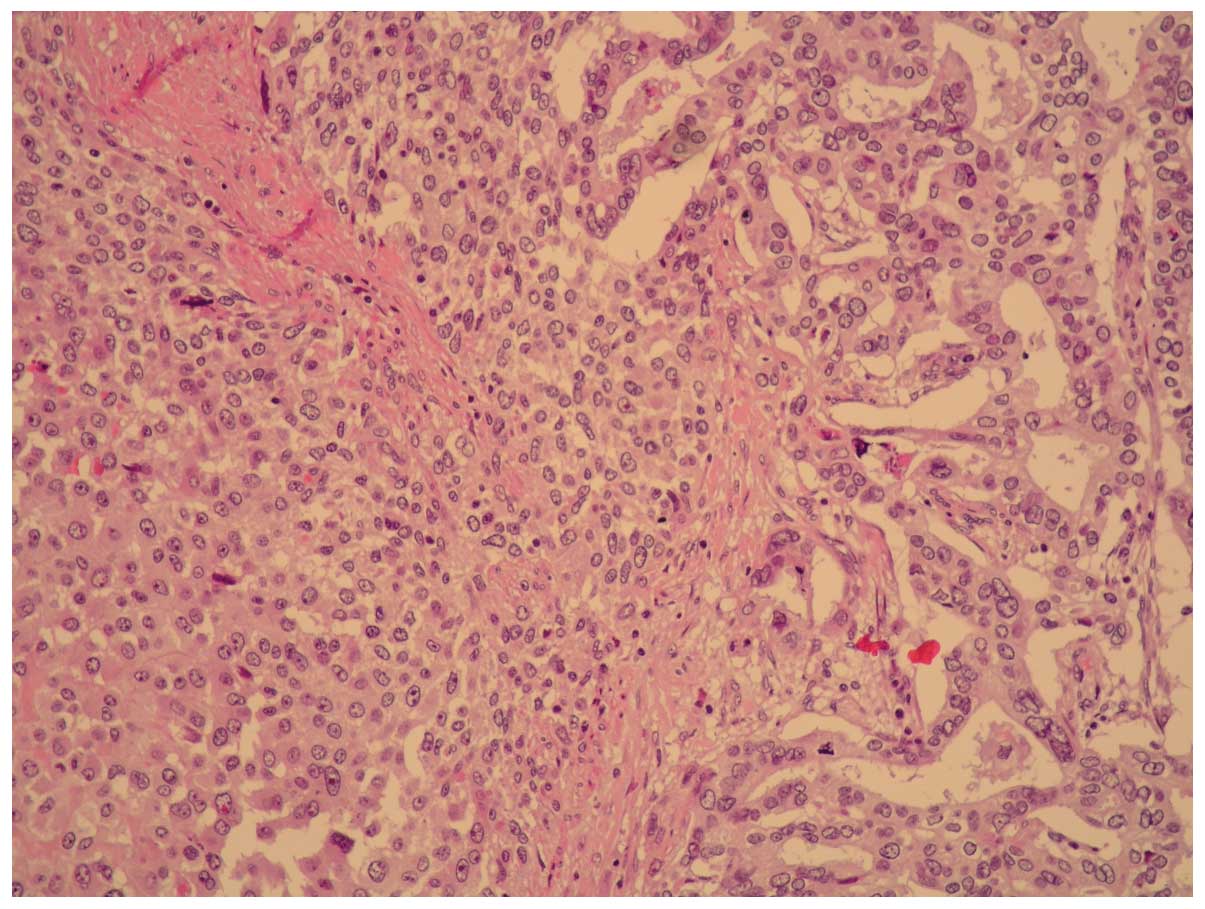

Microscopically, the tumor was composed of moderately

differentiated adenocarcinoma and poorly differentiated sarcoma

with a high mitotic index and necrotic areas (Figs. 1 and 2).

The tumor was found to have infiltrated the

perivisceral fat and peripancreatic areas. There was neoplastic

vein thrombosis of the splenic hilium and, for 2 of 13 regional

nodes, metastases were present (Fig.

3). These metastases belonged only to the carcinoma component

(pTNM classification was: T4 N1 G3 R0). The post-operative course